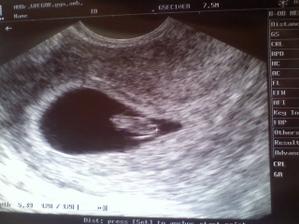

5. srp 2010

Jéé, máme stejný termín porodu. I když kdo ví, kdy se ten náš koblížek rozhodne na nás vykouknout, ale podle pana doktora je TP 8.12.2010 :D